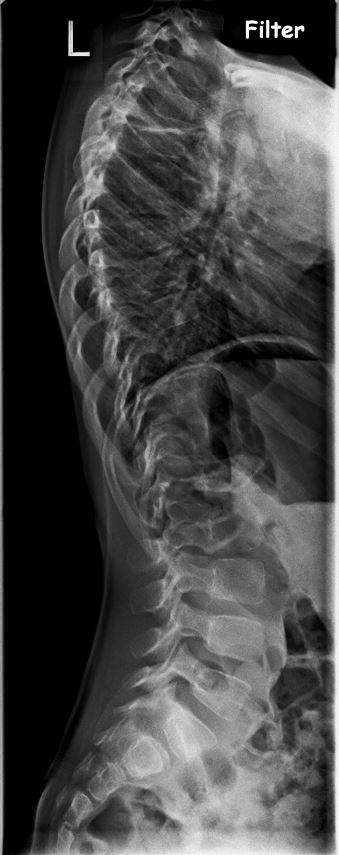

PS. Hier mal die RÖ-Bilder

Also für mich wäre das definitiv noch keine OP Indikation. Ich würde versuchen die Verschlechterung mit einem Korsett aufzuhalten. Wenn alles so bleibt werden mit hoher Wahrscheinlichkeit keine Probleme auftreten. Aufgrund der Höhe der Krümmung bei T6 geht sicher nur ein Nachtkorsett. Das sollte aber ausreichen. Sollte die Krümmung im Verlauf der Jahre doch zunehmen, kann man die Op immer noch durchführen. In der Regel kann der Verlauf jedoch gestoppt werden.

Ob da eine Korsettversorgung Erfolg bringen wird, hängt ganz von der Krümmung ab. Wobei BWK 6 schon sehr hoch ist. Haben Sie Rö.-Bilder?